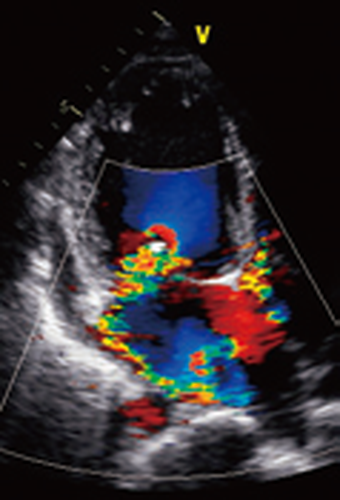

一般身体検査(聴診など)、血液検査、心電図検査、レントゲン検査、心臓エコー検査

エコー心臓・血管造影検査

心臓エコー検査・マイクロバブル造影法